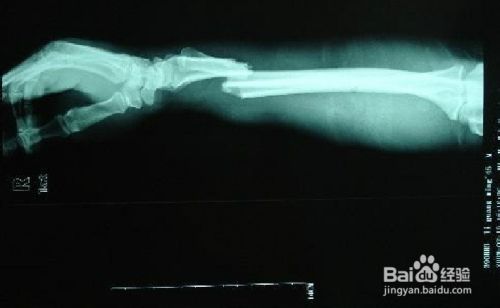

这第二个阶段为原始骨痂期,一般需4-8周,根据这名词就可以了解到,通过照的片可以看到骨折骨干四周包围有骨痂的阴影,骨折线也不完全消失的。这时候就可以拆除外固定,进行一定量的功能锻炼了。

第三阶段为骨痂改造塑型期,这个时期主要是将原始骨痂期所看到的骨痂改造成永久性的骨痂,并且这种骨痂是具有骨的正常结构的,这个过程成年人大约都需要8-12周。